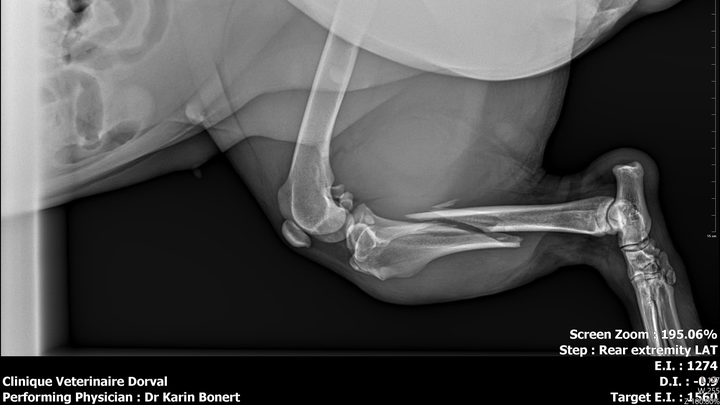

Recently, Shadow and I were involved in a terrible car accident that changed everything in an instant. Despite taking every possible precaution to keep her safe in the car, Shadow suffered a devastating injury and broke her leg. Seeing her in pain has been one of the most heartbreaking experiences our family has ever faced.

We rushed her to the vet immediately and did everything we could. We’ve already paid $1,000 for an emergency cast to stabilize her leg, but we were then told that she urgently needs surgery to properly heal. The cost of this surgery is $8,000, an amount we simply cannot afford on our own after everything we’ve already been through.